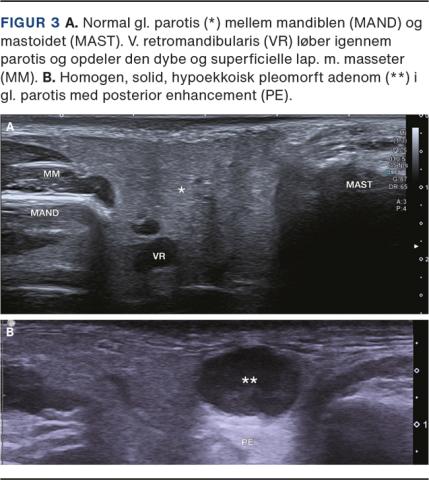

Skanning af gl. submandibularis (*) med tonsilla palatina (TONS) posterier herfor og m. digasticus venter posterior (DIG) og v. retromandibularis (VR) lateralt.

Traditionelt anvendes en række standardisererede sweeps for at sikre en systematisk UL-undersøgelse af hoved og hals, se tilhørende video [7] for gennemgang af UL-anatomi og skanningsteknik. Start med at skanne mundbunden fra midtpunktet af mandiblen og ned til os hyoideum i det tranverselle plan. Skan herefter gl. submandibularis igennem i det transverselle og longitudinelle plan og fortsæt til gl. parotis, der også skannes i begge plan. Skan nu ned igennem level 2-4 (Figur 1) med brug af a. carotis communis som orienteringspunkt i det transverselle plan. Skan supraklavikulært til level 5 og følg bagkanten af m. sternocleidomastoideus (SCM) eller forkanten af m. trapezius i det transverselle plan op til mastoidet. Herefter afsluttes UL-undersøgelsen af halsen med en gennemskanning midt på halsen fra os hyoideum ned til gl. thyroidea, som gennemskannes i to plan. Afslut med at skanne level 7 ned til jugulum sterni.